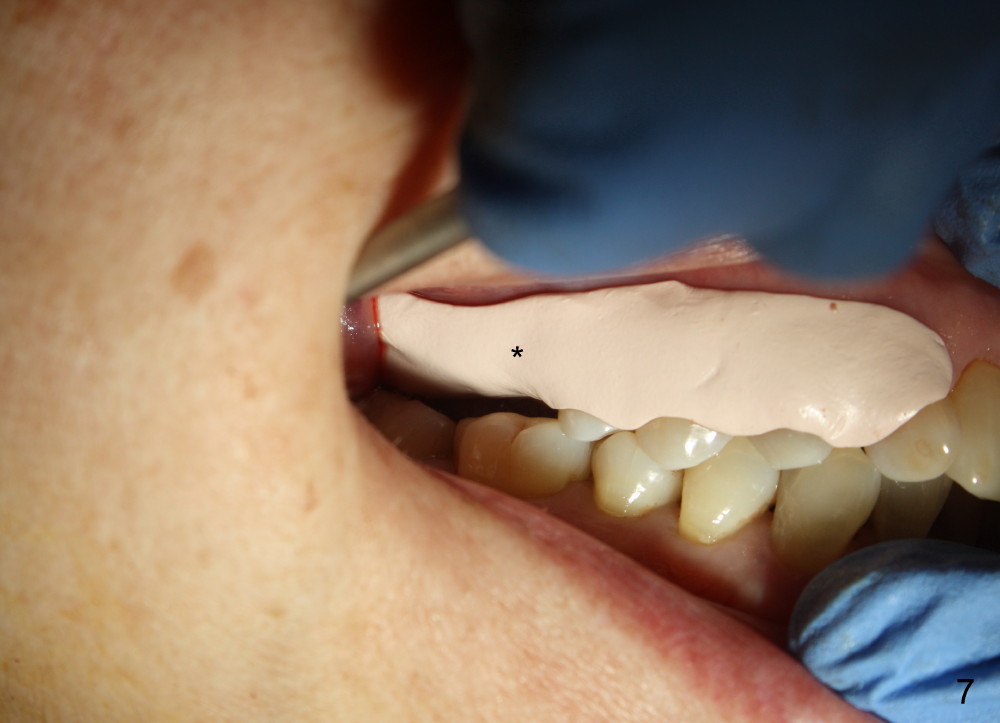

The upper right 1st molar fractures, the lingual portion mobile (Fig.1). There are deep pockets mesiolingually and distolingually. Fig.2 is preop PA, showing mesial bone resorption (*). The 84-year-old lady agrees extraction and immediate implant. Extraction is difficult due to not only root fracture but also hemorrhage. Following debridement of granulation tissue, the 3 sockets are packed with gauze for hemostasis. Even so, there is oozing from the bone. The septum can not be seen clearly. Its position is determined by an explorer. Osteotomes have to be used for osteotomy in the septum, followed by taps. The first intraop PA shows that 5x20 mm tap penetrates the sinus floor (Fig.3 ^). The osteotomy is further enlarged until 7x17 mm tap with stability (Fig.4). So far there has been no sign of sinus membrane perforation. Mixture of freeze dry mineralized bone and Osteogen is placed in the socket and pushed to the buccal and lingual walls as well as into sinus using a 4 mm flat end osteotome. A 7x17 mm implant is initially difficult to be inserted possibly due to blockage by bone graft. The osteotomy have to be recreated by a series of osteotomes and taps before placement of the 7x17 mm implant. It appears that the apical threads have been engaged into the sinus floor for primary stability (Fig.5). The insertion torque is 40 Ncm. According to our experience (1,2), this is not enough; finally the torque is increased to 60 Ncm by turning the implant more apically. The large implant obliterates the socket mesiodistally; the buccal and lingual gaps are filled with bone graft, followed by a collagen membrane (Fig.6 *) and suture. In order to protect the membrane, a short abutment is placed (A) and perio dressing (Fig.7*) is placed without occlusal interference. The abutment is removed 1 month postop, as the perio dressing has been dislodged. The patient returns for restoration 8 month postop. Bone regeneration occurs apparently in the coronal aspect of the implant (Fig.8), especially mesially (*, as compared to Fig.5). The gingiva-level implant is slightly subgingival mesially (Fig.9 M), probably due to high placement (compare to Fig.6). There is no bone resorption 6 months post crown (Fig.10 C) cementation.